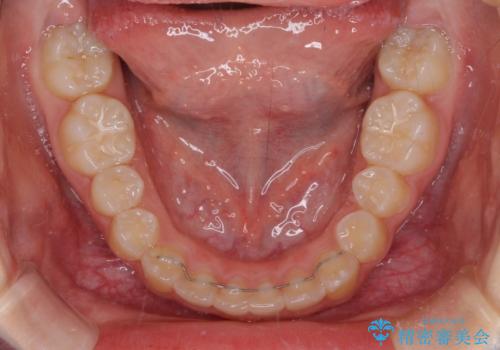

上下の骨幅を改善したことで、スムーズに歯列矯正を行うことができました。

インビザライン治療開始直後に遠方に引っ越しをされたため、通院間隔が長くなり、治療期間が長くなりましたが、しっかりと治療を行うことができました。